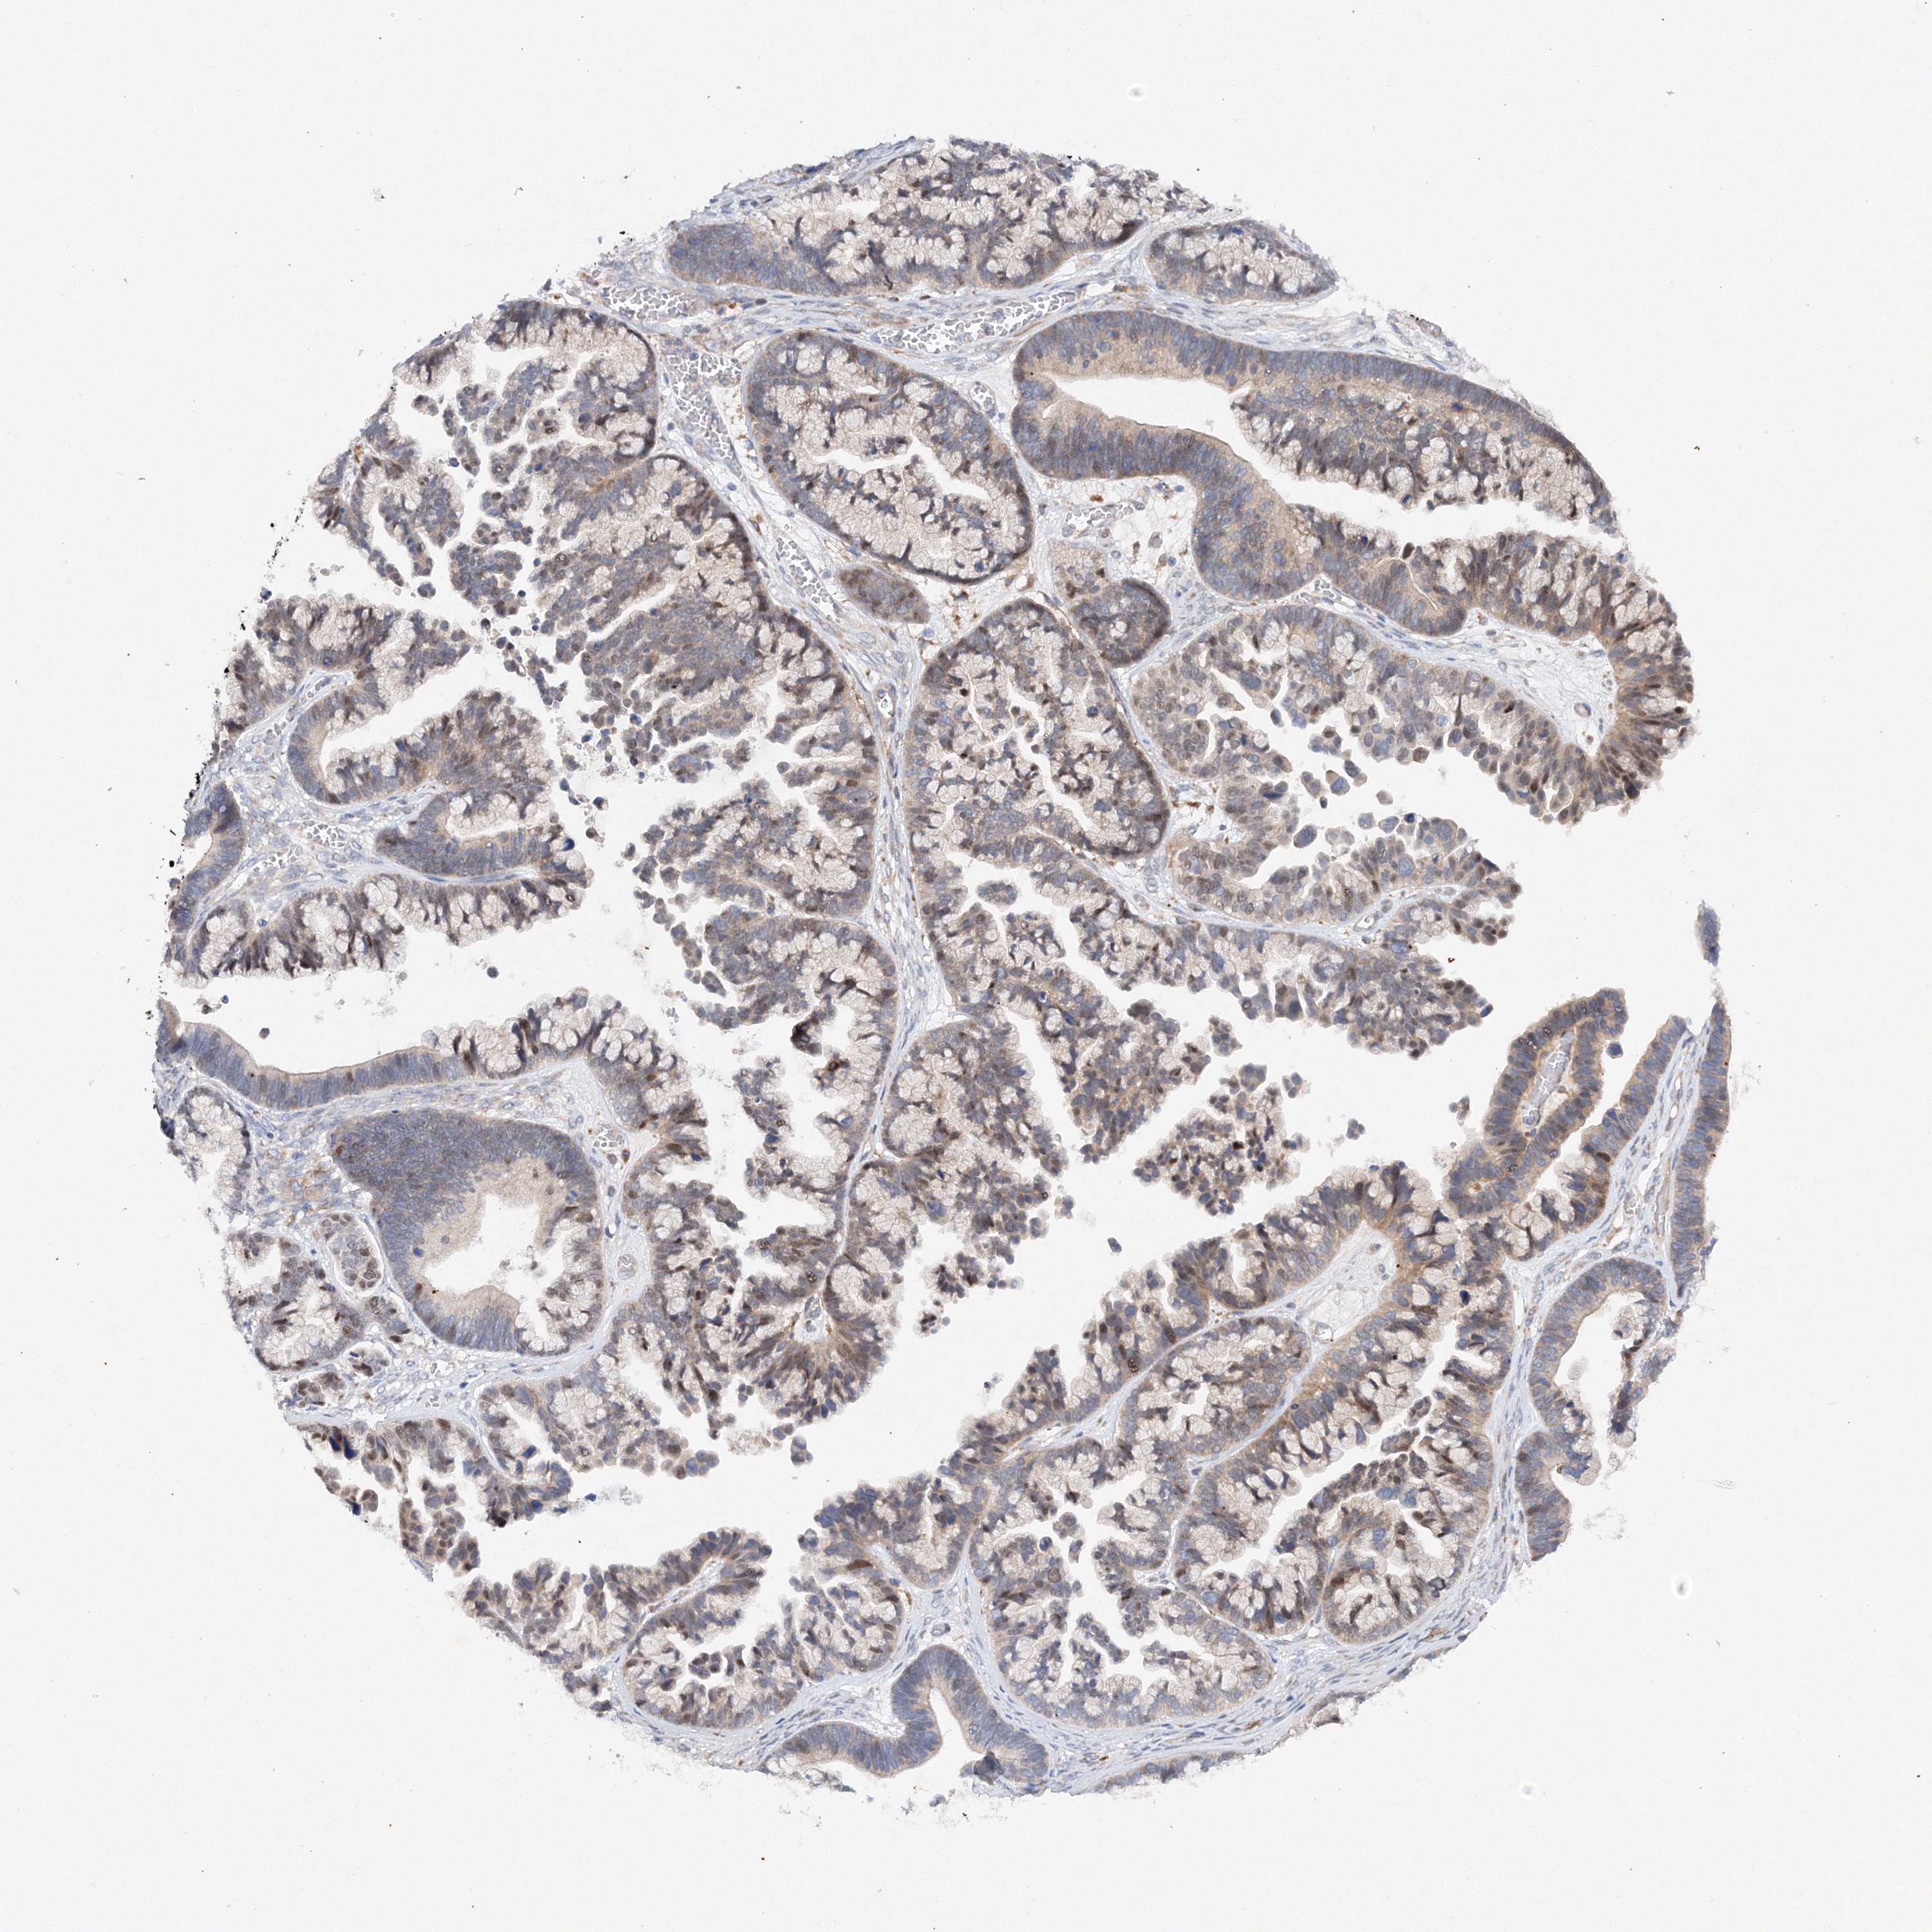

OVARIAN CANCER - Protein expressioni

A mouse-over function shows sample information and annotation data. Click on an image to view it in a full screen mode. Samples can be filtered based on level of antibody staining by selecting one or several of the following categories: high, medium, low and not detected. The assay and annotation is described here.

Note that samples used for immunohistochemistry by the Human Protein Atlas do not correspond to samples in the TCGA dataset.

Antibody stainingi

Antibody staining in the annotated cell types in the current human tissue is reported as not detected, low, medium, or high, based on conventional immunohistochemistry profiling in selected tissues. This score is based on the combination of the staining intensity and fraction of stained cells.

Each image is clickable and will lead to virtual microscopy that enables deeper exploration of all samples and also displays staining intensity scores, fraction scores and subcellular localization as well as patient and tissue information for each sample.

Antibody HPA035937

Staining

High

Medium

Low

Not detected

Intensity

Strong

Moderate

Weak

Negative

Quantity

>75%

75%-25%

<25%

None

Location

Nuclear

Cytoplasmic/membranous

Cytoplasmic/membranous,nuclear

Cystadenocarcinoma, serous, NOS

Carcinoma, endometroid

Cystadenocarcinoma, mucinous, NOS

Carcinoma, NOS